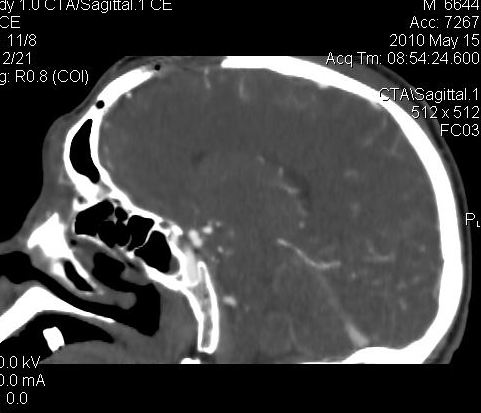

男.60岁,渐进性意识不清,ct检查双侧额颞顶部硬膜下血肿,开颅术后行脑血管cta,大脑中动脉起始部见一瘤状血管扩张。请各位老师留下宝贵意见

图片质量较差,是机器?